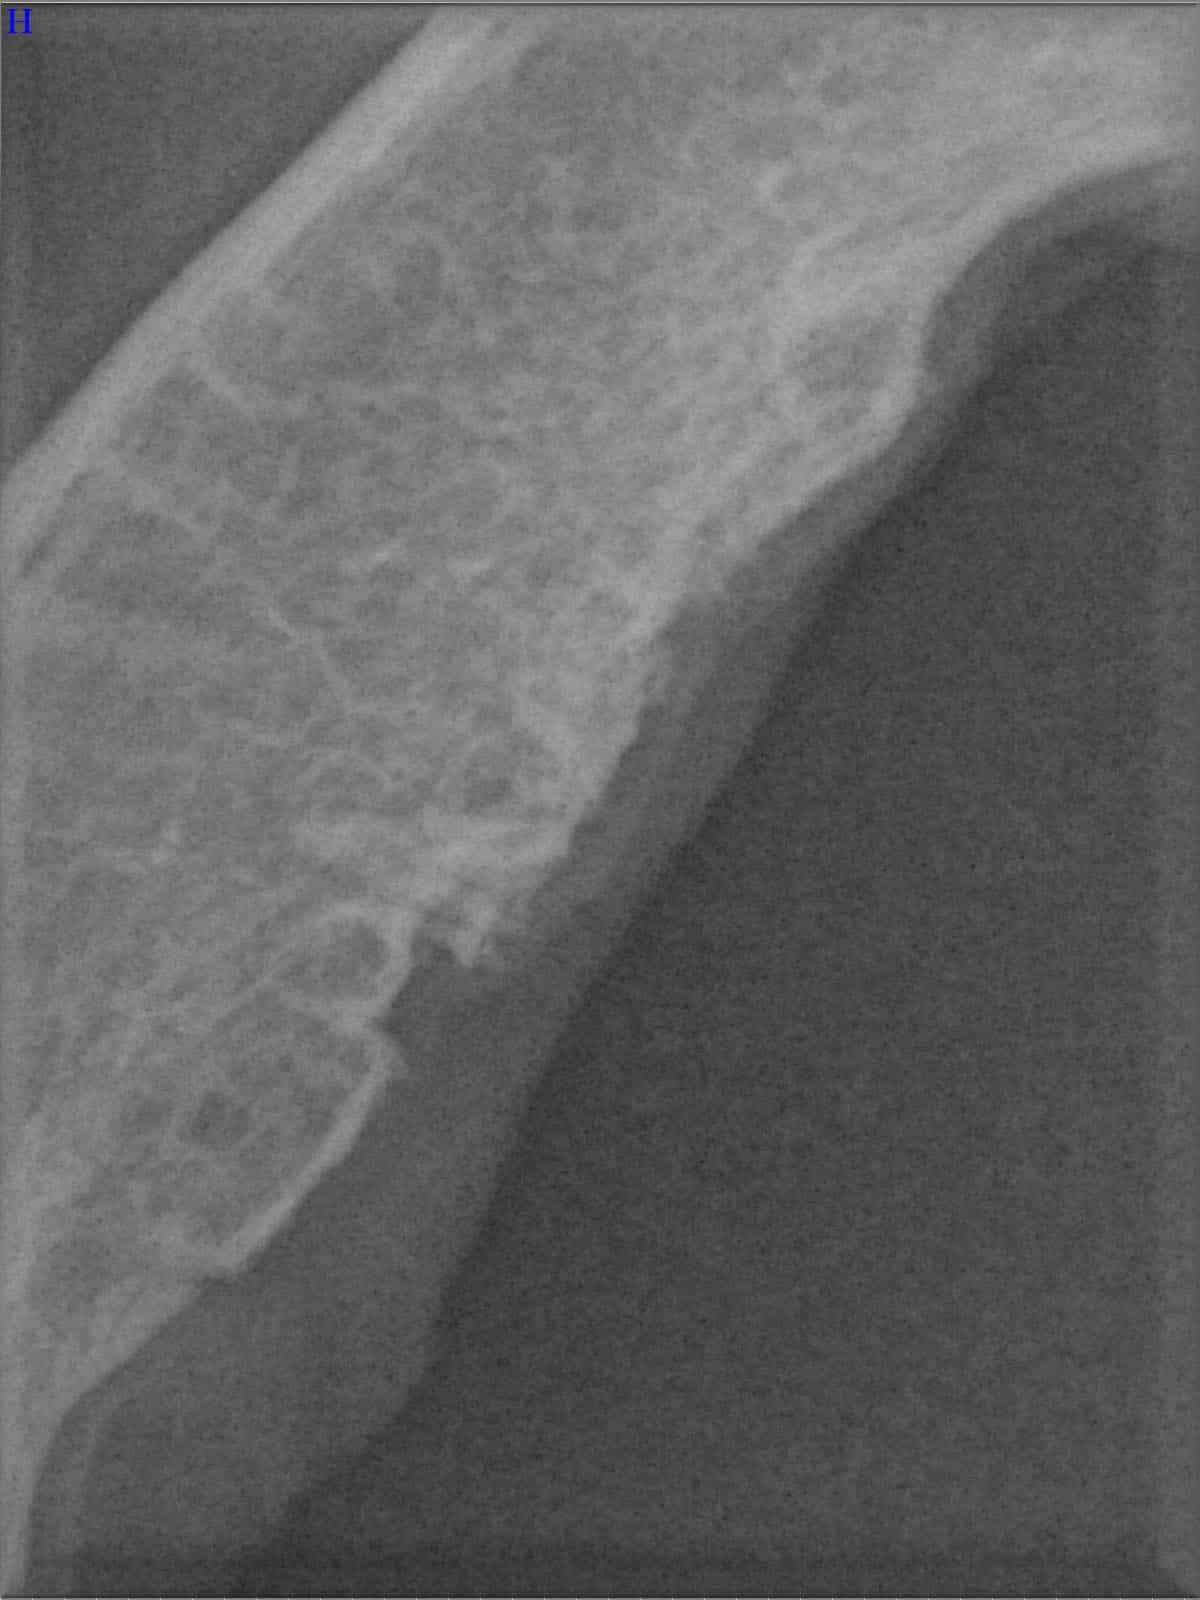

Ein entscheidender Baustein der FORL-Diagnostik ist das dentale Röntgen. Viele Läsionen sind von außen nicht sichtbar und lassen sich ausschließlich mithilfe moderner Röntgentechnik erkennen. In der Hamburger Praxis kommt digitales Dentalröntgen zum Einsatz, das detailreiche Aufnahmen bei geringer Strahlenbelastung ermöglicht. So kann FORL bereits in frühen Stadien diagnostiziert werden.

Das sehen Sie von außen – so sieht es auf den Röntgenbildern aus.

FORL Katze Röntgenbild

Röntgenbilder